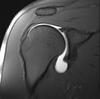

arrow demonstrates?

A, Normal infraspinatus muscle (arrow). B, Fatty infiltration of the infraspinatus muscle (arrow).